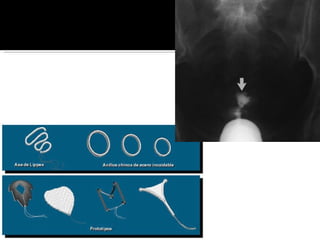

Criptomenorrea: 2ªria a un obstáculo congénito localizado en cualquier lugar de la vía de drenaje, cuello vagina o vulva,: himen imperforado, septum vaginal transverso y agenesia cervical. Pctes consultan por dolor intermitente, cíclico, tipo cólico intenso, gravativo a nivel del hipogastrio x la irritación peritoneal de la sangre regurgitada. Sensación de cuerpo extraño en hipogastrio, masa que aumenta progresivamente por distensión de vagina (hematocolpos), útero( hematometra), trompas (hematosalpinx).

Tratamiento es quirúrgico mientras mas rápido se opere y se drene la sangre, menor será el daño anexial.